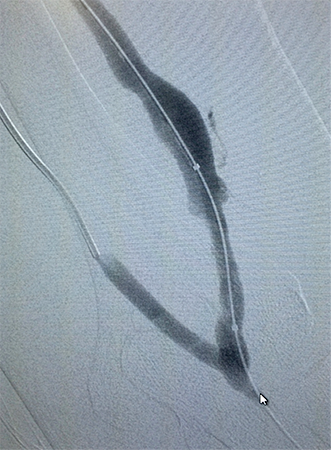

Tratamento de Aneurismas de Aorta, Periféricos ou Vicerais

É o tratamento de artérias dilatadas por métodos endovasculares pouco invasivos. O procedimento pode alterar de acordo com a região localizada, do tamanho e da condição do aneurisma. Atualmente a cirurgia vascular dispõe em seu arsenal para o tratamento de aneurismas, um método seguro e menos invasivo que a cirurgia convencional. O tratamento endovascular para aneurismas de aorta, viscerais e periféricos possibilita uma melhora na qualidade de vida dos pacientes de uma forma menos agressiva, objetivando evitar as principais complicações dessas doenças. São utilizados dispositivos de implante totalmente percutâneo e o procedimento é realizado em local específico para estes casos. Após detalhada análise de exames complementares: ultrassom, angiotomografia, angiorressonância, o cirurgião vascular opta pela melhor alternativa de tratamento baseado na anatomia da doença e no perfil de cada paciente.